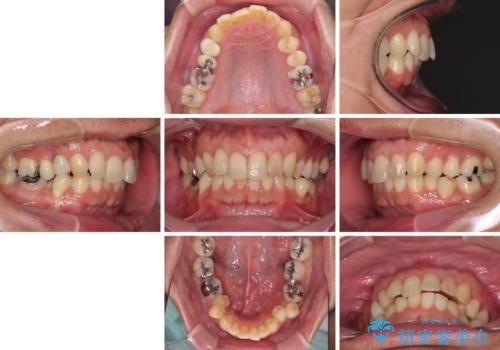

- 外に飛び出した側方の歯と、前歯のデコボコを気にして来院された患者様です。

IPR(歯と歯の間を削る)によってデコボコが解消するように設計し、インビザラインにより治療を行うこととしました。

治療途中で1年半以上通院されない時期があったため、後戻りが生じたことで治療期間が長くなってしまいました。

親知らずを抜去したことで、下顎のデコボコがきれいに解消されました。